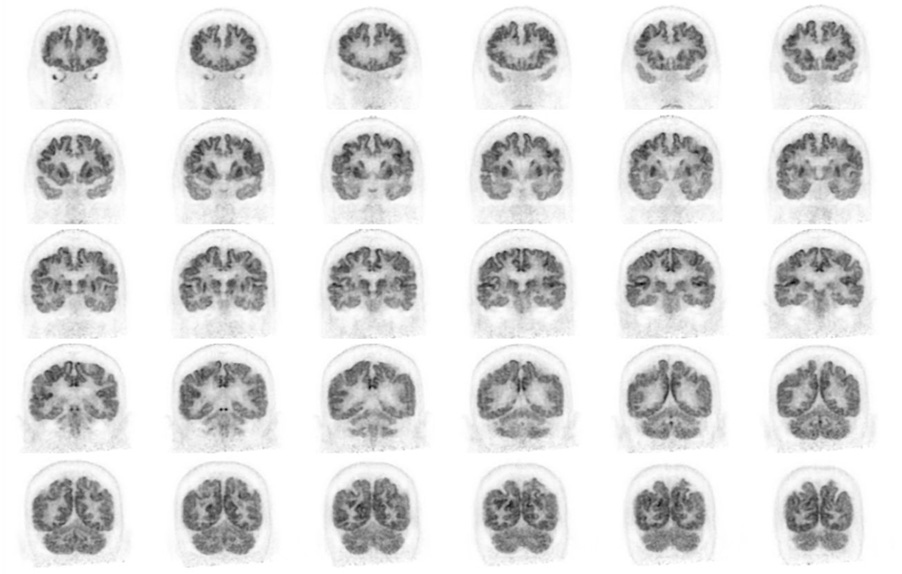

Head / Case3 : FDG

Coronal

Courtesy : Kindai University Hospital

- Imaging protocol

- Injected dose: 4.49 MBq/kg, 18F-FDG

- Uptake time: 46 minutes

- Scan time: 30 minutes